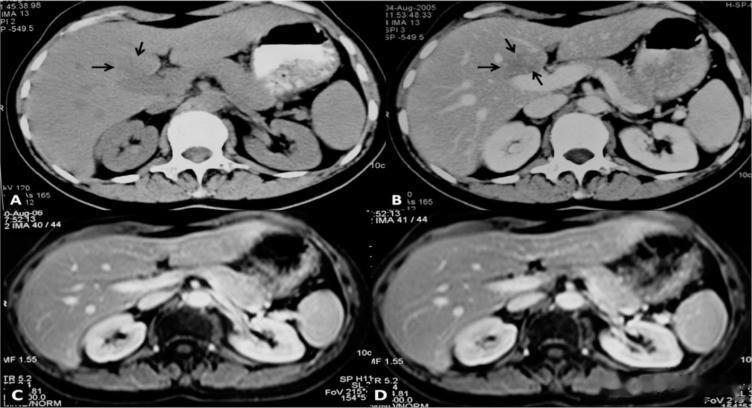

图为乳腺癌肝转移患者

接种前平扫(A)及增强扫描(B,静脉注射造影剂的门静脉期)轴向CT图像显示门静脉前方低密度病灶(箭头)。治疗后(1年后)相同解剖层面的增强T1-w磁共振连续图像(C、D)显示肝实质外观正常。